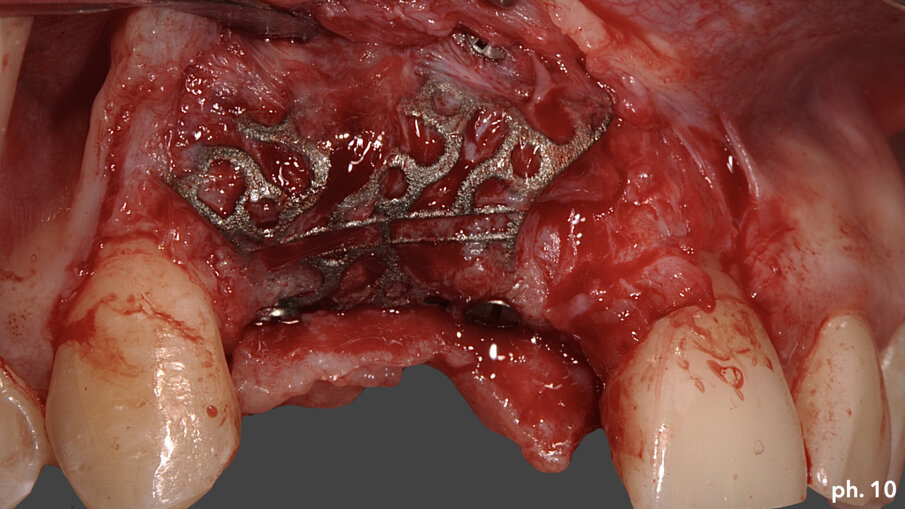

Una volta riempita la griglia con il mix di osso eterologo e autologo, la stessa è stata posizionata a livello del difetto e stabilizzata tramite l’utilizzo di viti di fissazione autofilettanti (Figg. 6, 7). Il grado di stabilità di queste griglie in titanio customizzate CAD/CAM è assolutamente elevatissimo, così come il loro grado di precisione. Stabilizzata in maniera perfetta la griglia, la stessa è stata ricoperta con uno strato di Geistlich Mucograft in modo da permettere la miglior maturazione possibile dei tessuti molli in fase di guarigione (Fig. 8). Al momento della chiusura del lembo è stato necessario effettuare un’incisione per il rilascio del periostio per ottenere una guarigione per prima intenzione, aspetto fondamentale affinché la maturazione di tali presìdi risulti perfetta. Il tempo di guarigione suggerito dalla letteratura prima della rimozione della griglia è di circa otto mesi; personalmente aspetto sempre 12 mesi prima di inserire impianti in una zona di osso rigenerato, e così è stato anche in questa situazione. L’immagine numero 9 rappresenta la guarigione a un anno di distanza e la relativa radiografia di controllo (Fig. 9). L’attesa così prolungata porta a far sì che la fase chirurgica della rimozione delle griglie in titanio sia l’aspetto più complesso di tutto il trattamento. Questo perché le aderenze di tipo fibroso che si creano tra i tessuti molli e la griglia stessa rendono difficile l’asportazione soprattutto a livello palatale e linguale (Fig. 10).